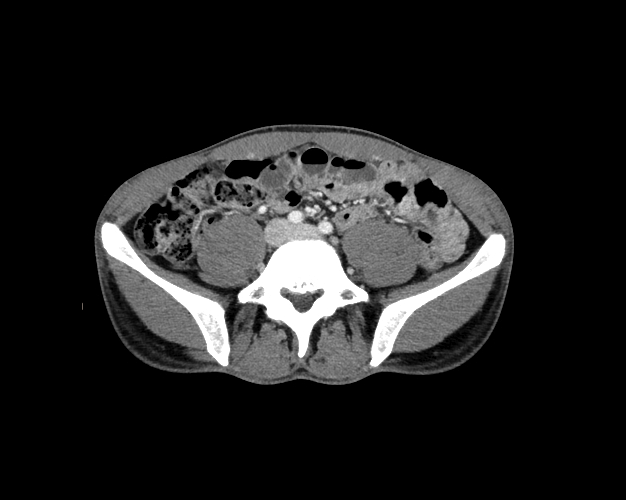

Body

Covers abdominal CT anatomy.